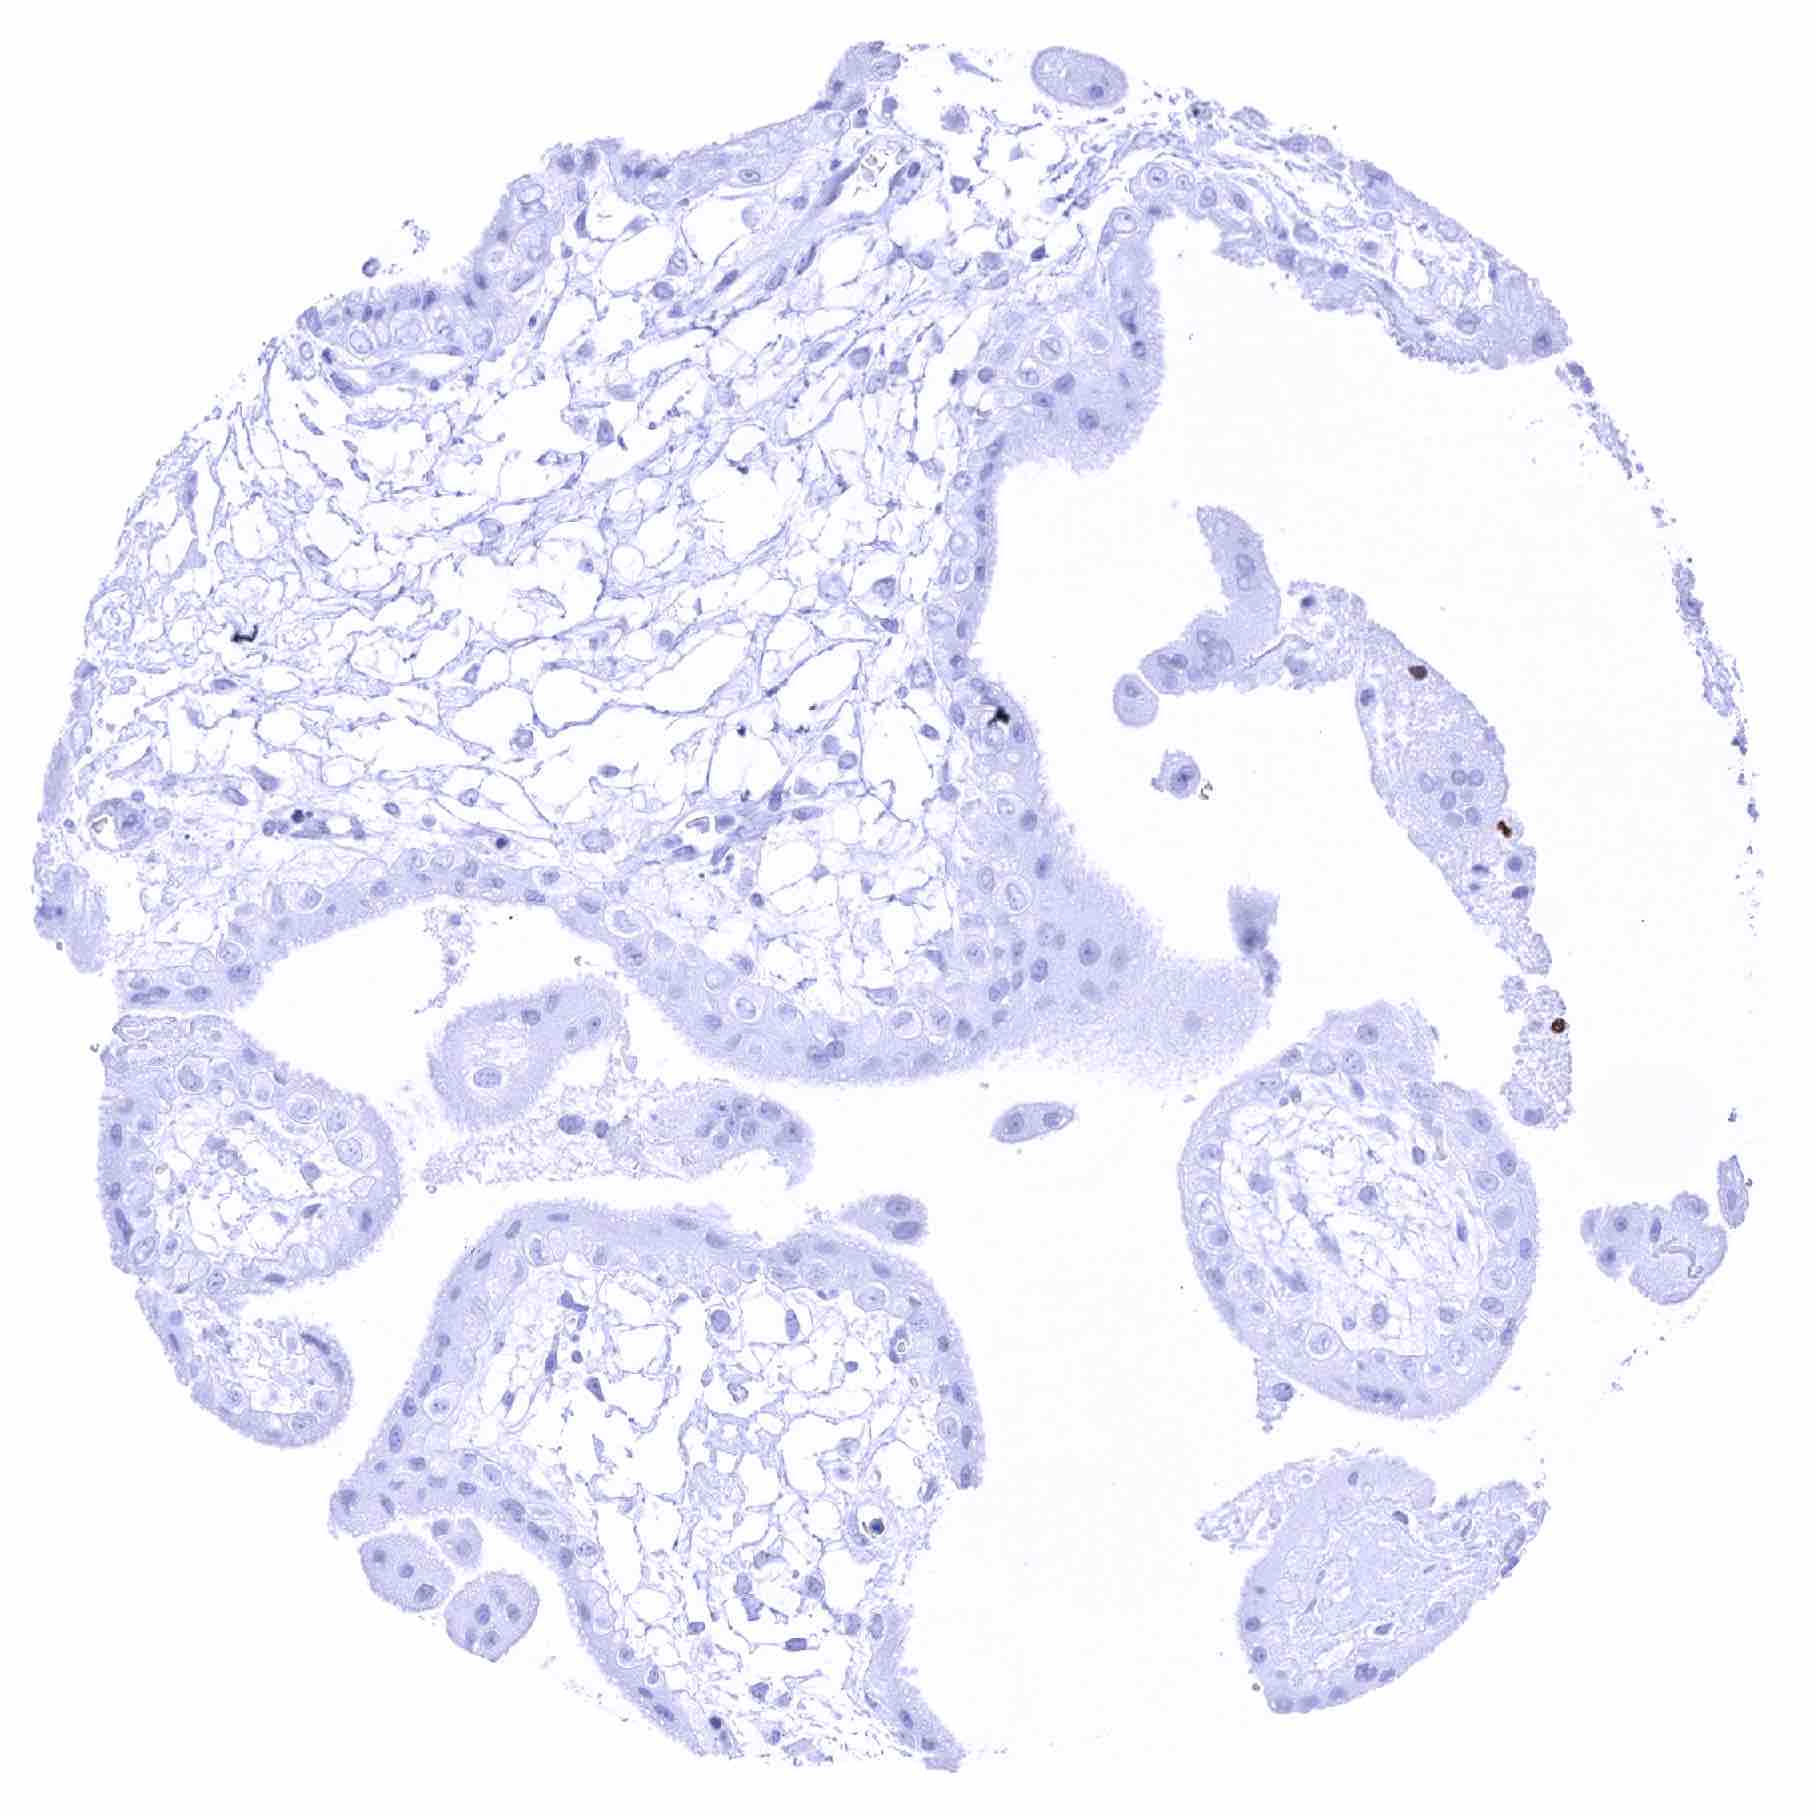

Placenta, early